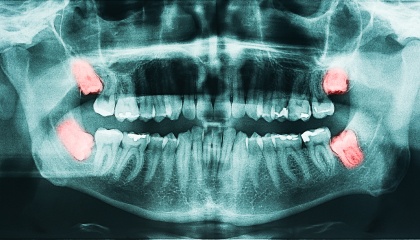

Wisdom Teeth Removal Made Easy

before

after